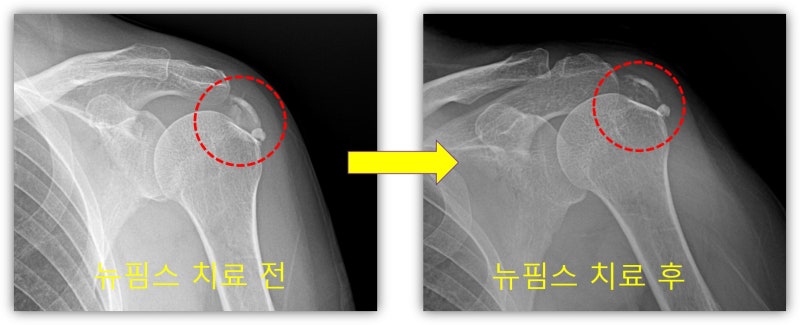

안녕하세요. 이번에는 석회성 건염으로 병원을 내원하신 환자에게 뉴핌스 치료를 한 사례를 보여드리겠습니다. 66세 여자 환자 분으로 6개월간 좌측 어깨 통증이 심하게 있으셨고 타 병원에서 아플때 주사만 맞았던 환자 였습니다. 최근들어 통증이 너무 심해져서 내월 2일 전에도 타병원에서 주사를 맞았으나 전혀 호전이 안되어 저한테 내원하였습니다. 통증이 너무 심하여 이학적 검사를 하지 못했고 x-ray 상 어마어마한 석회성 건염이 관찰되었습니다.

사진과 같이 석회분쇄흡입술을 시행하여 많은 양의 석회를 제거하였습니다.

뉴핌스 치료 후 사진과 같이 석회가 많이 제거된 x-ray 를 확인할 수 있습니다. 조금 석회가 남아 있으나 향 후 체외충격파 치료를 추가적으로 시행하면 완전히 제거가 될 것으로 사료됩니다. 환자는 시술 다음날 부터 통증이 거의 없고 팔도 잘 움적여 진다며 환하게 웃으십니다. 석회성 건염 치료는 그냥 통증만 제어한다고 해결되지 않습니다. 석회를 제거해야만 석회성 건염에서 탈출할 수 있습니다. 석회성 건염은 뉴핌스치료가 탁월한 효과를 보입니다. 이제 석회성 건염의 고통에서 수술 없이 완전히 벗어날 수 있습니다.